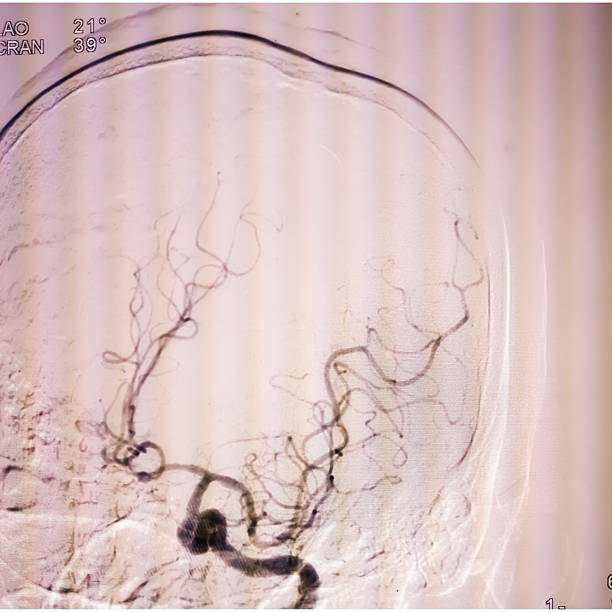

🟢 뇌경색이란 무엇인가요?

뇌경색은 뇌혈관이 막히면서 해당 부위에 혈액이 공급되지 않아 뇌세포가 손상되는 질환이에요.

**‘허혈성 뇌졸중’**이라고도 하며, 전체 뇌졸중의 약 **70~80%**를 차지할 만큼 흔한 형태입니다.

보통은 고혈압, 당뇨, 고지혈증, 흡연, 심장질환 등이 주요 원인으로 작용하죠.